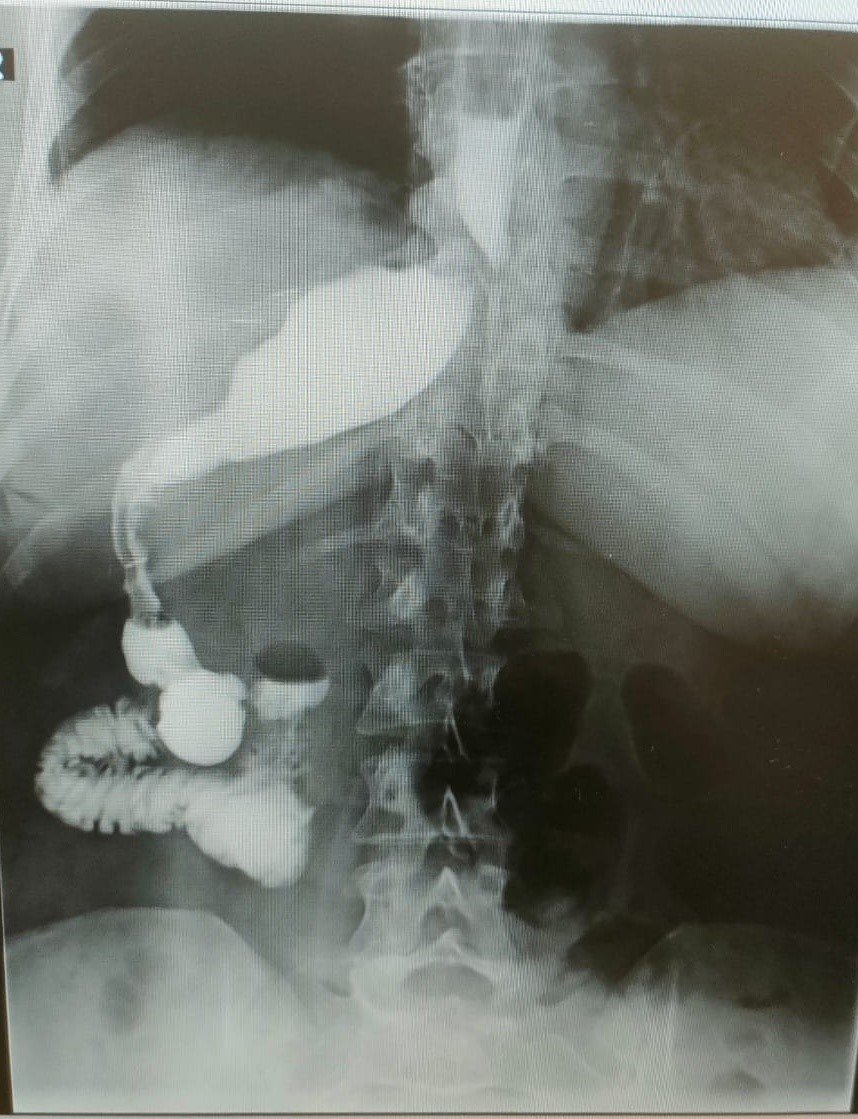

Almanya'dan tüp mide ameliyatı olmak için Antalya'ya gelen 46 yaşındaki hemşire Antje Kirscht, eşine az rastlanır bir tıbbi durumla karşılaştı. Antalya'da özel bir hastanede gerçekleştirilen operasyon sırasında Kirscht'in midesini olması gerektiği yerde göremeyen doktorlar kısa süren şaşkınlığın ardından mideyi karaciğerinin arkasında, sağ tarafta buldu. Mide başarılı bir operasyonla küçültülürken bu sıra dışı anatomik durumun, dünyada yalnızca 100 binde bir görüldüğü biliniyor.

Almanya'da hemşire olarak görev yapan Antje Kirscht, tüp mide ameliyatı olmak için sosyal medyada yaptığı araştırmalar sonucunda Memorial Antalya Hastanesi Genel Cerrahi Bölüm Başkanı Prof. Dr. Alihan Gürkan'a ulaştı. İlk kez Antalya'ya gelen 46 yaşındaki Kirscht, 110 kilo ağırlığıyla obezite tedavisi için başvurdu. Almanya'da kendisine organlarının ters olabileceği yönünde bir tanı konduğunu ifade eden Kirscht, bu bilginin ameliyat sırasında ne anlama geldiğini öğrendi. Ameliyat esnasında cerrahi ekip, Kirscht'in midesini karaciğerinin arkasında, sağ tarafta buldu. Bu sıra dışı anatomik durum, hem hasta hem de ekibin şaşkınlık yaşamasına neden oldu.

Ameliyatı gerçekleştiren Memorial Antalya Hastanesi Genel Cerrahi Bölüm Başkanı Prof. Dr. Alihan Gürkan, yaşadıkları şaşkınlığı şu sözlerle dile getirdi: "Çok yapılan bu operasyonlar içerisinde hastanın değişik bir anomalisi vardı. 100 binde bir görüldüğü söyleniyor. Organların hepsi ters olabiliyor. Bu daha sık görülen bir şey ama bu hastada bütün organlar yerli yerinde ama sadece mide sağ tarafa kaymış. Yani karaciğerin arkasına gitmiş. Operasyona başladığımızda mideyi bulamadık. Karaciğeri kaldırınca mideyi sağ tarafta gördük. Bu çok nadir bir durum. 2023 yılı verilerine göre, böyle bir tüp mide ameliyatı dünyada yalnızca 50 kişiye uygulanmış. Biz de bu vakayı başarıyla gerçekleştirdik. Teknik açıdan bizi zorlayan ancak deneyimimizi artıran bir ameliyat oldu".

Prof. Dr. Gürkan, ameliyatın detaylarına değinerek, "Tüp mide operasyonunun ayna görüntüsünü yaptık. Normalde sol tarafta yaptığımız obezite ameliyatını bu hastada sağ tarafta gerçekleştirdik. Midenin karaciğerin arkasında olması ameliyat süresini 15 dakika uzattı ve toplamda 1 saat sürdü. Bizim için de hoş bir tesadüf oldu" diye konuştu.